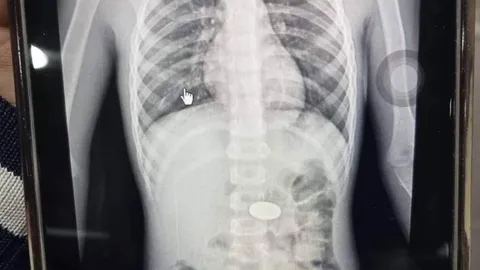

แม่เล่าอุทาหรณ์ ลูกชายอมเหรียญ 5 แล้วพลาดลงคอ เอกซเรย์พบอยู่ในหลอดอาหาร